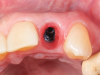

Fig 7. A case (Fig 7 through Fig 16) is presented demonstrating construction of a fixed provisional temporary crown at site No. 10, beginning with an implant placed at the site.

Figure 7